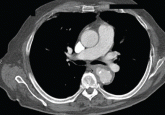

ArticleSalmonella-related mycotic pseudoaneurysmAuthor:Bacel Nseir, MDPublish date: May 1, 2009A 74-year-old man is admitted to the hospital with a 7-day history of fever, rigors, chest pain, and general weakness. He underwent coronary artery...Read More